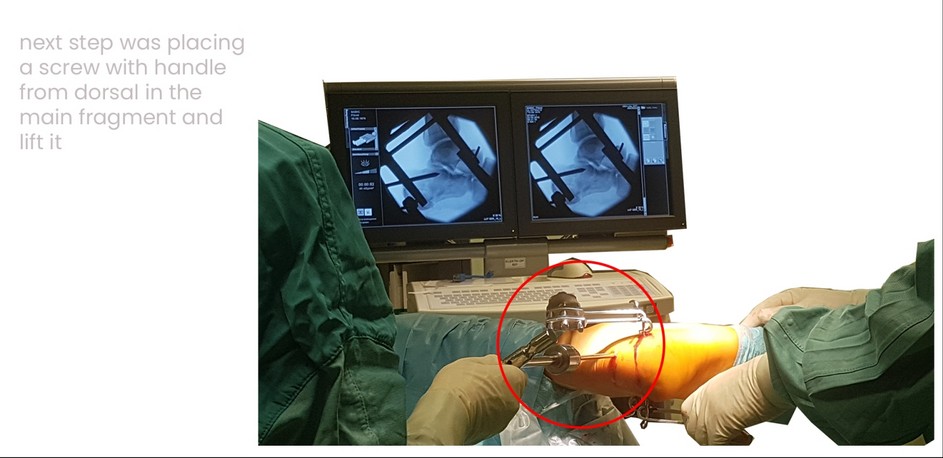

back Case 18SF, male 42 years , tonque-type right, depression-type left, surgery one day after trauma, show you surgery on right side, reduction in combination extension and after Westhues